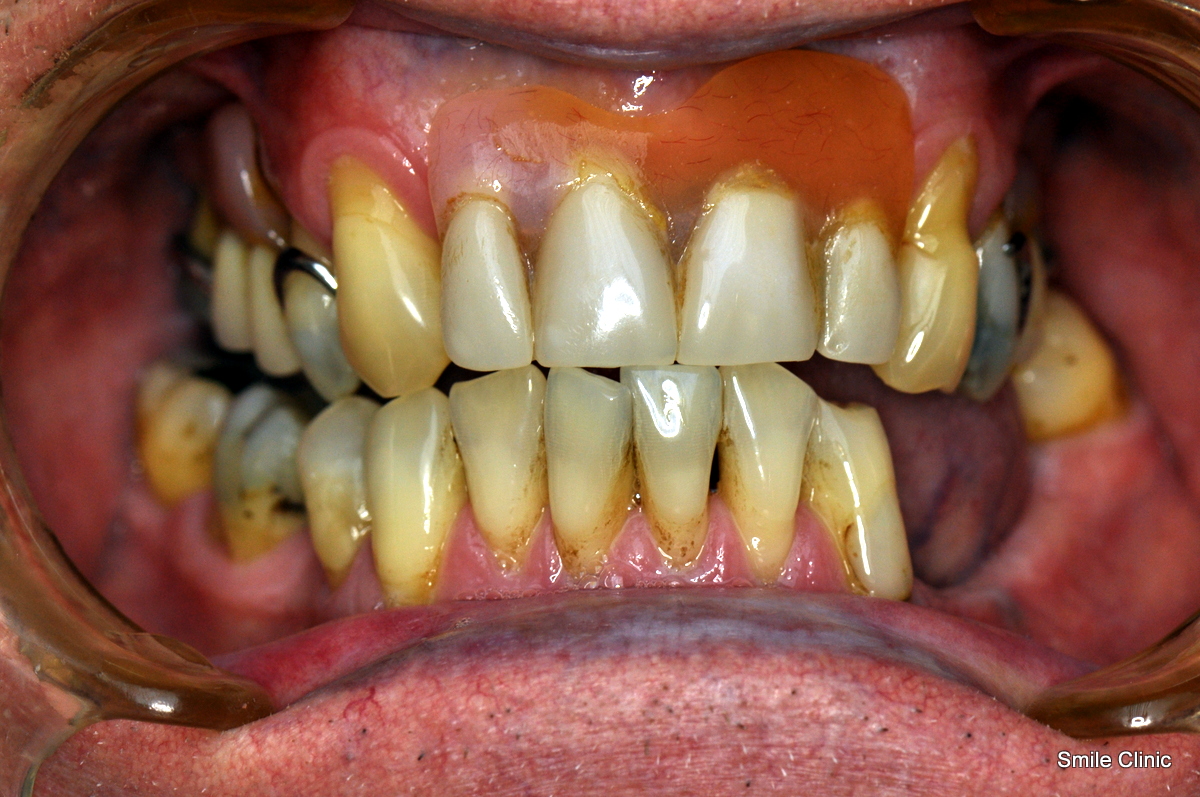

He had been wearing false upper teeth for some time, and decided to finally get rid of it by opting for the “all on 6” dental implant procedure giving him 12 new, fixed teeth for his upper jaw on 6 dental implants, as well as a crown tooth bridge of 4 teeth for the bottom jaw towards the back for added eating strength.

As you can see from the photographs, David opted for a natural look, complementing his original teeth – with an improved smile & confidence.

For many years I have had dentures which were uncomfortable and ugly to look at.